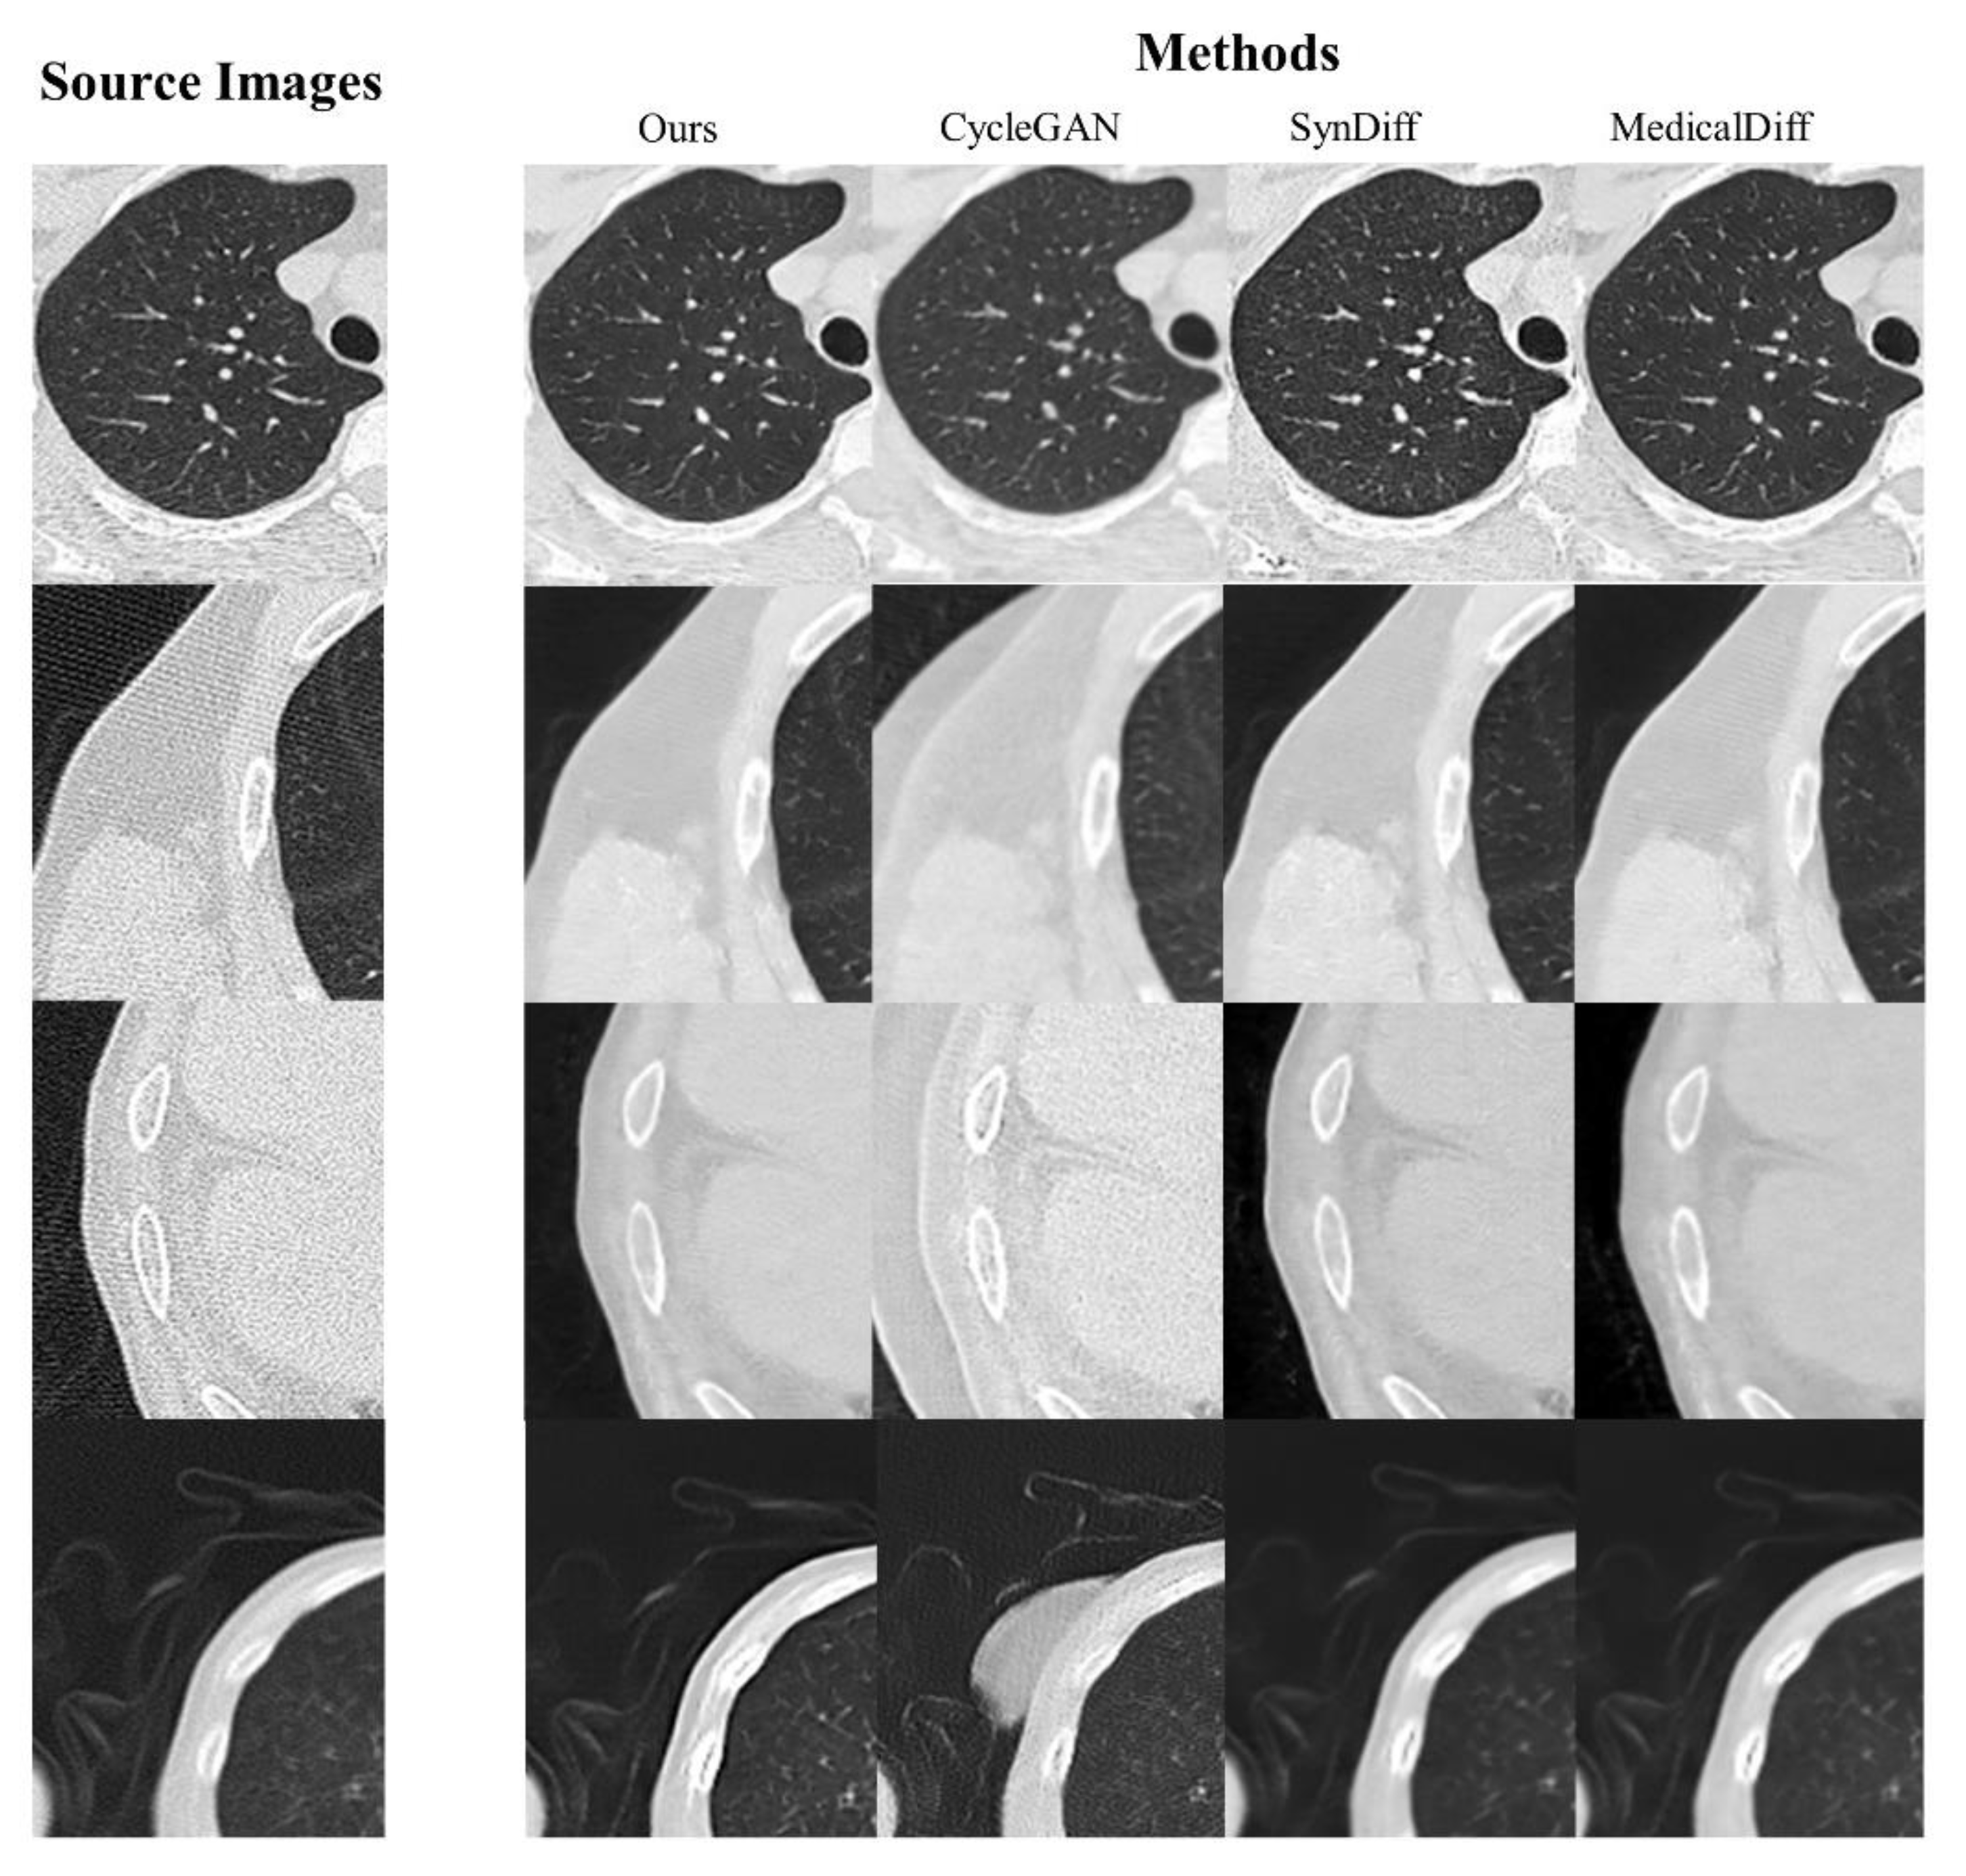

| Ours | CycleGAN | SynDiff | CoreDiff | |

|---|---|---|---|---|

| Lung PSNR | 37.822±0.74 | 35.196±0.63 | 36.177±0.84 | 37.356±0.49 |

| Lung SSIM | 0.869±0.03 | 0.855±0.03 | 0.859±0.06 | 0.855±0.02 |

| Trachea PSNR | 35.998±0.35 | 33.903±0.50 | 34.693±0.66 | 35.310±0.46 |

| Trachea SSIM | 0.843±0.02 | 0.810±0.04 | 0.833±0.07 | 0.828±0.03 |

| Overall PSNR | 36.952±0.67 | 34.776±0.81 | 35.722±0.93 | 36.498±0.55 |

| Overall SSIM | 0.863±0.01 | 0.835±0.09 | 0.856±0.07 | 0.851±0.01 |

| Lung DSC | 0.986±0.095 | 0.939±0.161 | 0.988±0.203 | 0.979±0.091 |

| Trachea DSC | 0.933±0.041 | 0.890±0.780 | 0.929±0.125 | 0.931±0.027 |

| Bones DSC | 0.961±0.023 | 0.912±0.058 | 0.955±0.031 | 0.940±0.022 |

| Overall DSC | 0.959±0.134 | 0.932±0.206 | 0.953±0.318 | 0.951±0.126 |